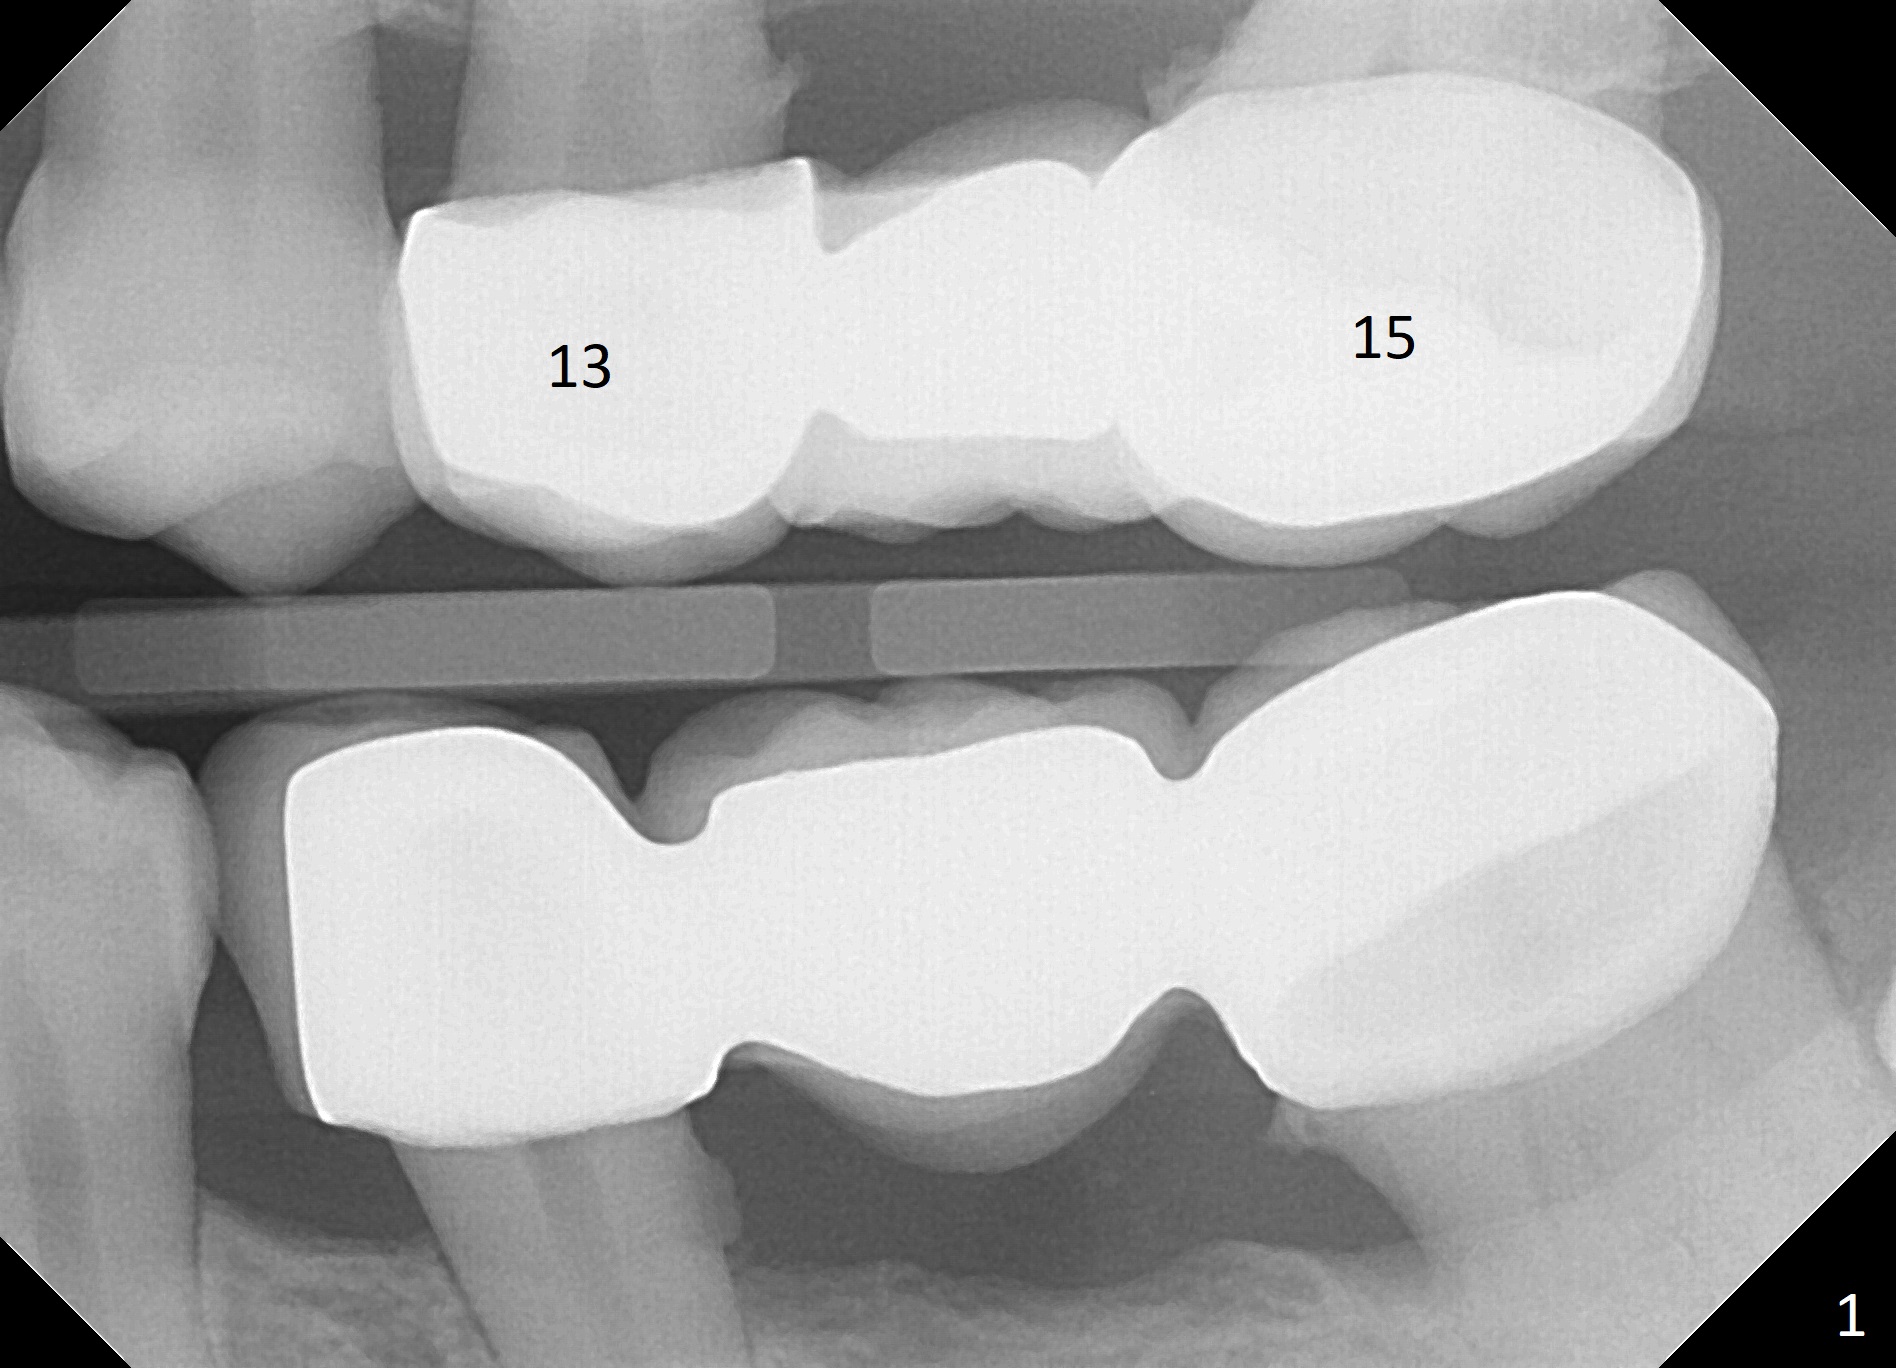

A 50-year-old woman has multiple restoration (Fig.1,2). There is discomfort with the upper left FPD, which will be removed (without local anesthesia initially) for exploration and SRP. Use a metal quadrant tray to take Alginate impression prior to FPD removal. If the abutments at #13 and 15 are to be extracted, an IS implant will be placed at the edentulous area. If the ridge is narrow and the bone is soft, use DIO bone expanders. If one or both of the abutments are non-salvageable, place UF immediate implant(s).